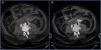

Varón de 56 años con espondilitis anquilosante y anticoagulado, que ingresa tras ser atropellado por un vehículo. A su llegada, en situación de shock hipovolémico, requiere transfusión masiva y administración de fármacos vasoactivos. Eco-FAST negativo. En el TAC se objetiva rotura aórtica, secundaria a lesión espinal por mecanismo de flexión-distracción. En las figuras 1 y 2 se observan cortes axiales con contraste intravenoso (CIV) en fase arterial (A), fase portal (B) y sagital en fase arterial (C), a nivel de L2-L3. La aorta abdominal presenta abundante material hiperdenso adyacente correspondiente a CIV extravasado (flechas) en retroperitoneo, espacio intersomático y al espacio epidural. El paciente es sometido a cirugía urgente, falleciendo periprocedimiento (figs. 1 y 2).